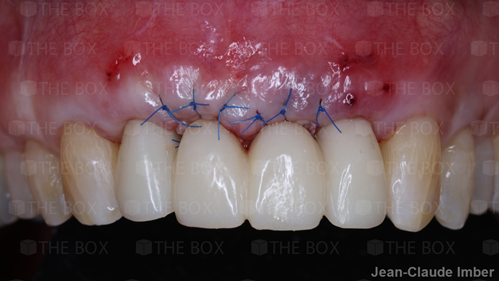

A new case was made public by Jean-Claude Imber check it out here.